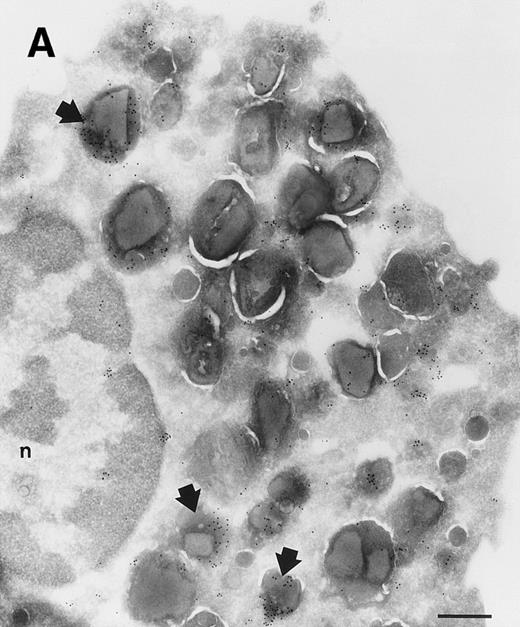

Immunoelectron microscopic studies on the localization of sPLA2 in human eosinophils.

Investigation of the intracellular localization of sPLA2 in unstimulated eosinophils was undertaken by immunoelectron microscopy (immuno-EM). Immunogold-labeled MoAb against sPLA2 was detected in granules that contained the typical eosinophil crystals (Fig 2). It is difficult to ascertain whether the heterogeneity in the labelling in the granules is due to heterogeneity in the localization of sPLA2 or to partial destruction of the epitopes for the antibody due to the fixation procedure used.

Localization of sPLA2 in human eosinophils isolated from peripheral blood. Ultrathin cryosections were incubated with MoAb 10B2, rabbit antimouse IgG and goat antirabbit IgG conjugated to 10-nm gold particles. (A) Overview of an eosinophil showing labeling mainly on the matrix of specific granules, although these granules do show heterogeneity. Nucleus (n); bar = 500 nm. (B) Detail of the cytoplasm showing dense labeling in some granules (closed arrows) and absence of label in others (open arrows). Bar = 200 nm.